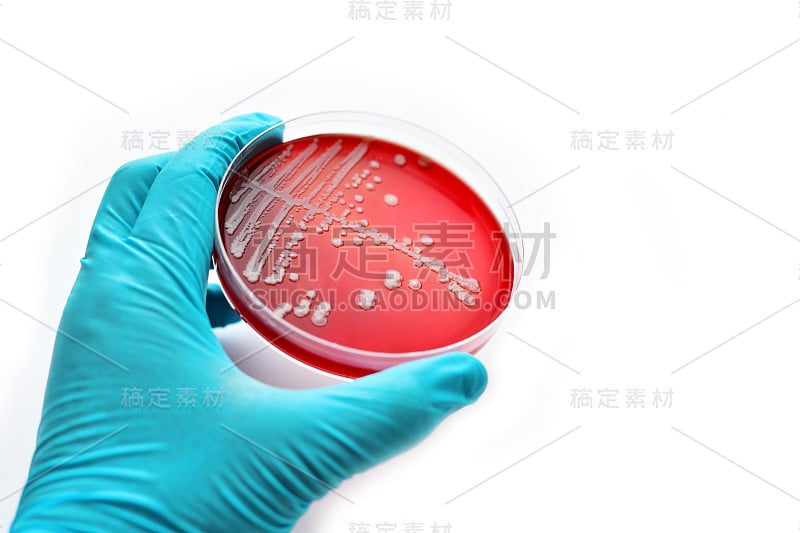

培养基板上的细菌菌落详情

细菌菌落详情

细菌培养详情

细菌培养详情

细菌培养详情

细菌培养详情